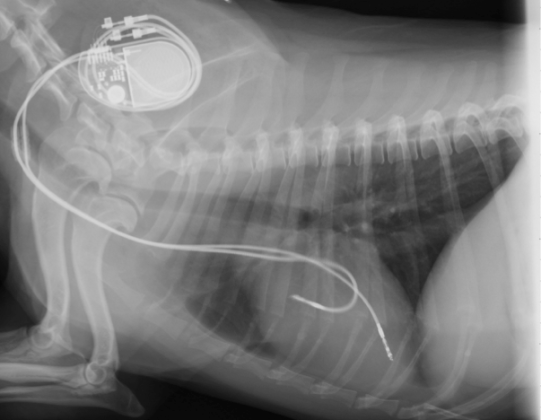

Therapie der Wahl für einen AV-Block 3. Grades wäre die Implantation eines Herzschrittmachers (z.B. an der Herzabteilung des Tierspitals Zürich). Hierbei wird ein künstlicher Taktgeber unter die Haut implantiert, welcher über einen oder zwei feine Drähte mit dem Herzen verbunden wird und so eine normale Schlagfrequenz erstellt. Die Besitzer entscheiden sich jedoch aus verschiedenen Gründen gegen diesen Eingriff. In der Folge geht es Jari erstaunlich gut, obwohl er v.A. zu Beginn immer wieder Schwächeepisoden zeigt; in gewissen Fällen kann das Herz nämlich das Problem mittels einem erhöhtem "Lade-Blutdruck" im Herzen und damit einer effizienteren Pumpaktion eine ganze Weile kompensieren.

Röntgenbild eines Hundes mit Schrittmacher (Copyright Dr. N. Hildebrandt, Universität Giessen) - es handelt sich hier natürlich nicht um Jari